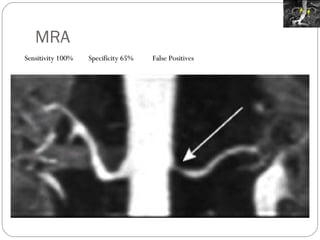

MRA Sensitivity 100%  Specificity 65% False Positives